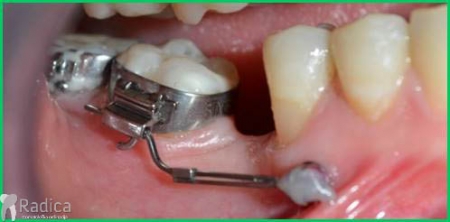

U ovom slučaju je 41.godinu starom pacijentu počeo nicati impaktirani desni gornji očnjak pri čemu je ugrozio lateralni sjekutić. Pacijentu je stavljen fiksni aparat te je zub smješten u luk. Kako je pacijent odustao od postave aparata u donjoj čeljusti na kraju nije dobivena zadovoljavajuća okluzija na što je upozoren.